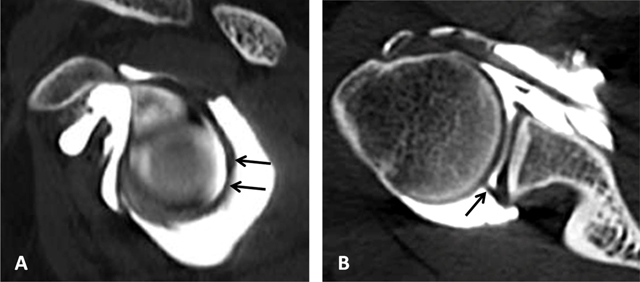

Figure 20

Middle glenohumeral ligament. The midsection of the ligament often adopts a more horizontal course. This can result in a thinner, wavier appearance on axial fat-saturated proton density MRA image (arrows, B) with a longer section of the ligament (arrows) on CTA (A).